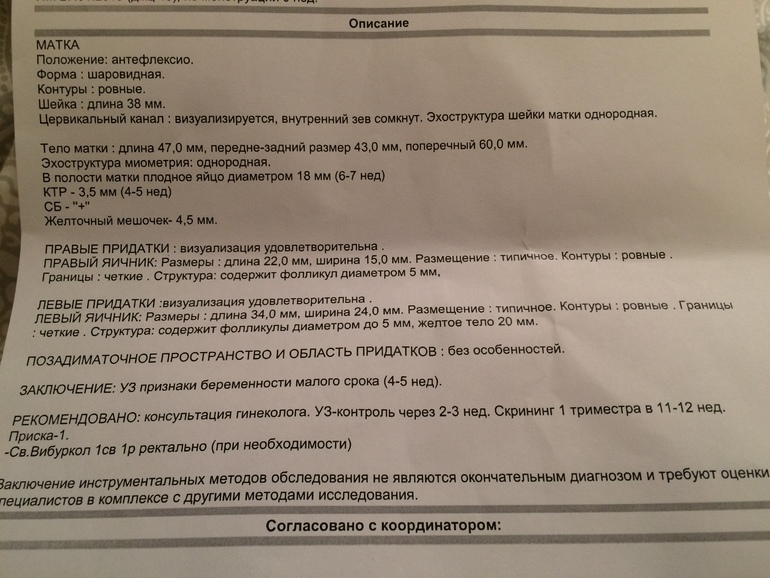

Это наше первое узи, в 5 недель и 6 дней акушерских.

Смущает что ПЯ 18 мм соответсвует сроку 6-7 недель а КТР 3,5 мм на 4-5 недель. Это нормально? Сердцебиение есть , не слушали но доктор сказала что есть.